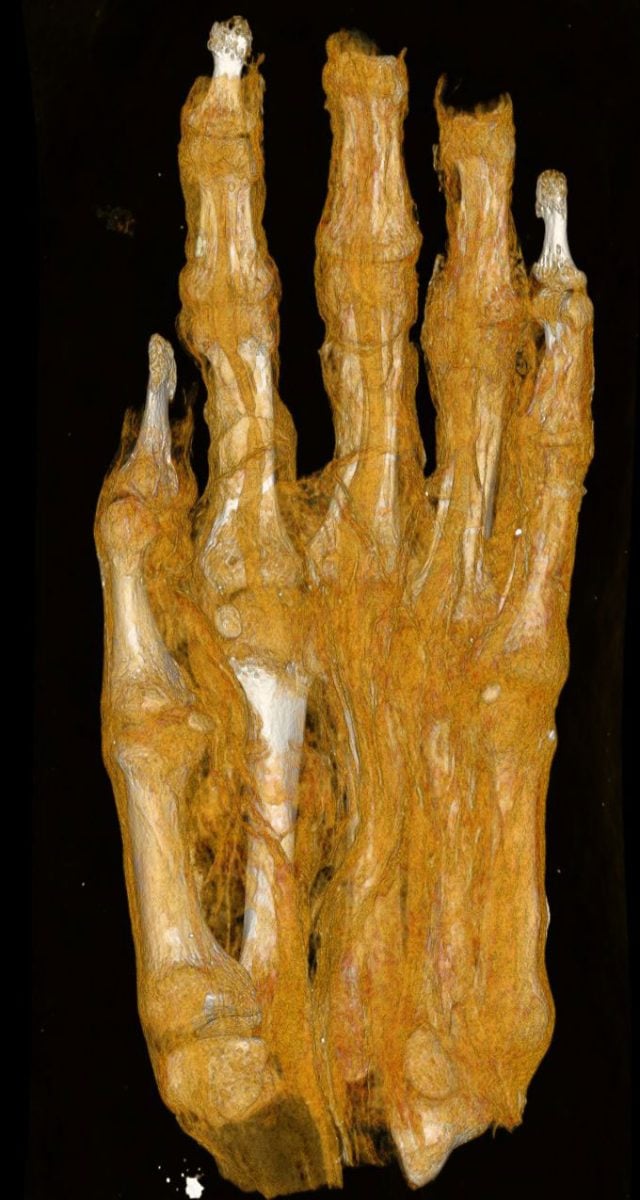

Another set of remains, once thought to be a simple mummy bundle, has produced surprising results. When it first entered the collection, it was identified as a human head and later possibly as a bird mummy. A previous CT scan clarified that it is actually an adult foot.

Mummification Techniques and Tissue Analysis

Researchers are also examining how textile fragments can reveal details about mummification practices, the individual’s age, and possible health conditions. The scans clearly show multiple layers of wrapping and their structural differences, which could support further historical and technical studies. The remains were likely once part of a complete mummy, though when and why they were separated is still unknown.